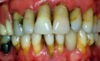

Clinical health vs gingivitis vs periodontitis